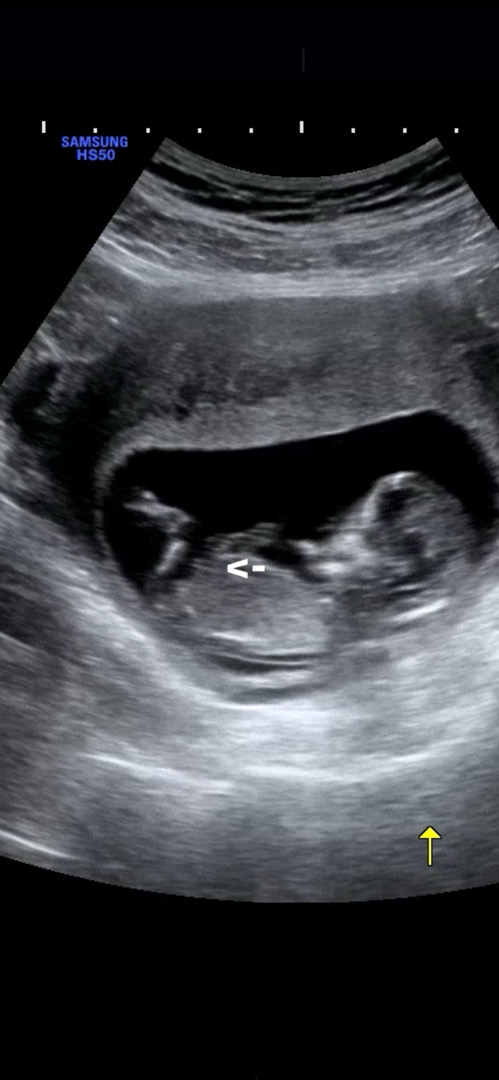

12주3일차 각도법 봐주세요!!!

딸인거 같은데 댓글 마구 부탁드려요^^ 각도법과 끝 갈라짐이 딸인거같은데 기대해도 될까요!?!?ㅎㅎㅎㅎ

저긴 생식기가 아니에요

저 위치면 탯줄 같은데욤...? 제 눈엔 생식기 부분은 안 나온 것 같습니다ㅎㅎㅎㅎ